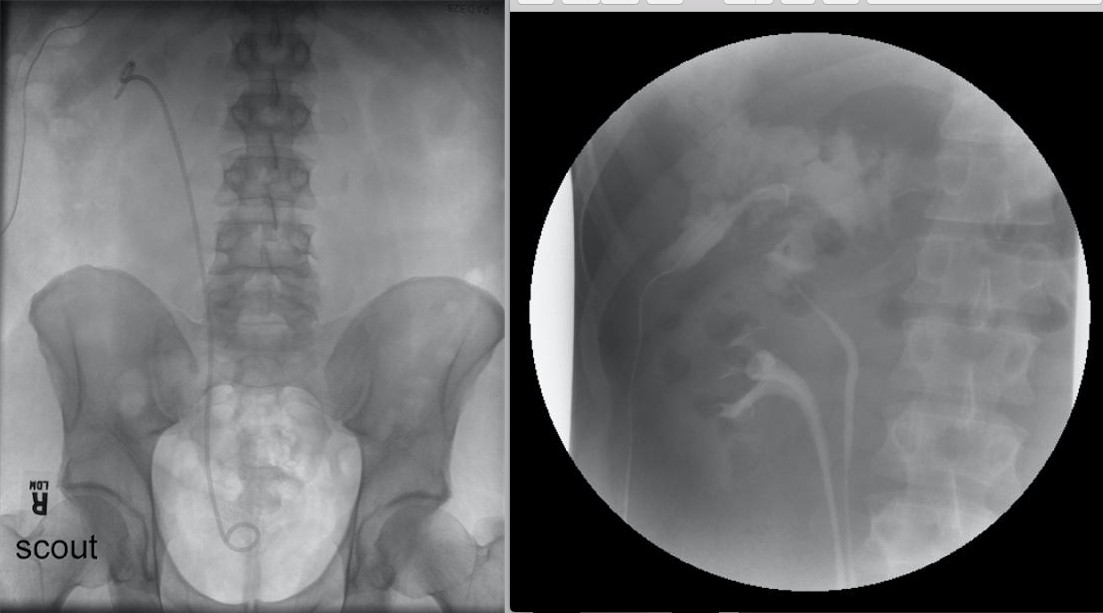

A 67-year-old man has persistent urinary drainage from a flank drain ten days following laparoscopic partial nephrectomy for a 3 cm upper pole mass. A retrograde ureteral stent was placed at the time of surgery. A KUB and renal image during cystography are shown. The next step is:

4

Following partial nephrectomy, a urinary fistula can develop in up to 17% of patients. This patient has persistent urinary drainage from his partial nephrectomy site despite placement of a ureteral stent. The radiographic studies demonstrate an incomplete duplication of the ureter with the stent in the lower pole moiety. The upper pole system (the site of the partial nephrectomy) remains unstented with persistent drainage. Observation will likely not improve the problem, and the drain should be left alone. The best treatment would be to reposition the stent into the upper pole collecting system and placement of a urethral catheter. Once the drainage stops, the urethral catheter can be removed, followed by the removal of the drain at a later date. The ureteral stent should be removed last. Greater than 99% of urinary fistula following partial nephrectomy resolve either spontaneously or with endoscopic management.